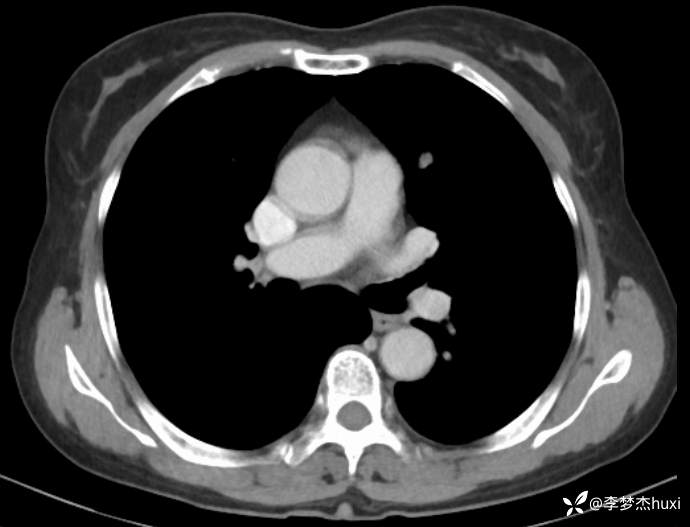

1.现病史:患者老年 女,患者于入院前3天(2024-06-02)体检查胸部CT:左肺部分实性结节,右肺磨玻璃结节,左肺上叶实性结节--性质?建议肺结节门诊会诊检查;双肺索条,双肺下叶条絮状高密度影--考虑肺血坠积效应,主动脉壁钙化,双侧胸膜局部增厚,左侧乳腺钙化点。2024-06-04查胸部增强CT:左肺上叶实性结节--占位?建议结合病理;左肺部分实性结节,右肺磨玻璃结节,建议肺结节门诊会诊检查;双肺索条,主动脉壁钙化,双侧胸膜局部增厚,左侧乳腺钙化点。患者目前无咳嗽、咳痰,无发热,无胸痛,今为求进一步诊治来我院,门诊以“肺诊断性影像异常”收入院。

4.辅助检查:2024-06-02查胸部CT:左肺部分实性结节,右肺磨玻璃结节,左肺上叶实性结节--性质?建议肺结节门诊会诊检查;双肺索条,双肺下叶条絮状高密度影--考虑肺血坠积效应,主动脉壁钙化,双侧胸膜局部增厚,左侧乳腺钙化点。2024-06-04查胸部增强CT:左肺上叶实性结节--占位?建议结合病理;左肺部分实性结节,右肺磨玻璃结节,建议肺结节门诊会诊检查;双肺索条,主动脉壁钙化,双侧胸膜局部增厚,左侧乳腺钙化点。。